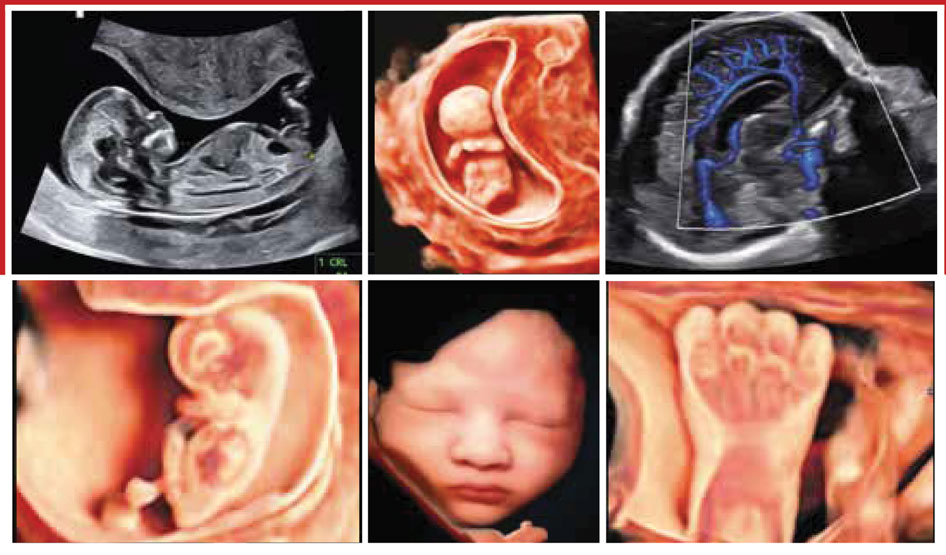

Echo Anatomie Normale et Pathologique du FŒTUS

Echographie